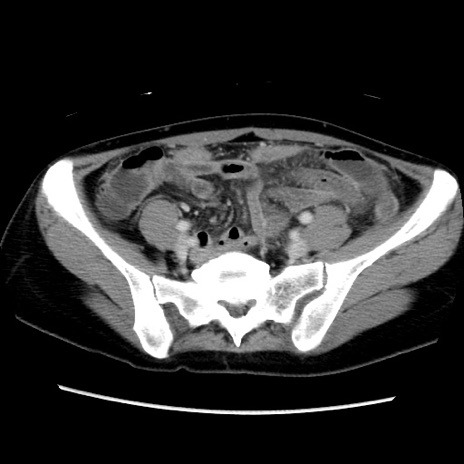

症例39(横断像)

【症例】40歳代女性

【主訴】上下腹部痛

【現病歴】2日目から下腹部痛あり。夜間は痛みで眠れなかった。昨日より上腹部痛と下痢が出現。臥位で痛みは軽快したため、休んでいた。本日になって臥位でも立位でも痛みが強くなってきたため救急要請。

【既往歴】子宮内膜症

【身体所見】部:平坦・軟、左上下腹部に圧痛あり、反跳痛あり。

【データ】WBC 21800、CRP 26.78